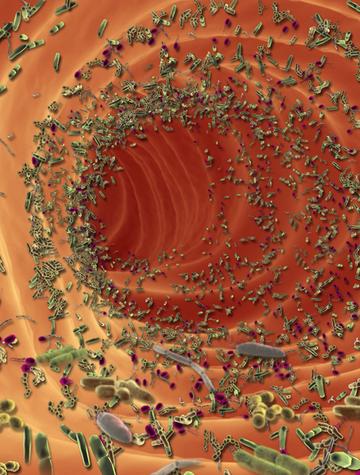

Le microbiome et son impact sur l’allergie digestive

Le microbiote est aujourd’hui reconnu comme un « organe » à part entière qui constitue l’un des piliers de la santé humaine. Le microbiome (du grec micro, « petit » et bios, « vie ») est l’« aire biotique » (aire de vie) du microbiote, désignant ici les espèces autrefois regroupées sous le terme « microflore », c’est-à-dire celles qui prédominent ou sont durablement adaptées à la surface et à l’intérieur d’un organisme vivant. C’est dans cette perspective que deux équipes [...]